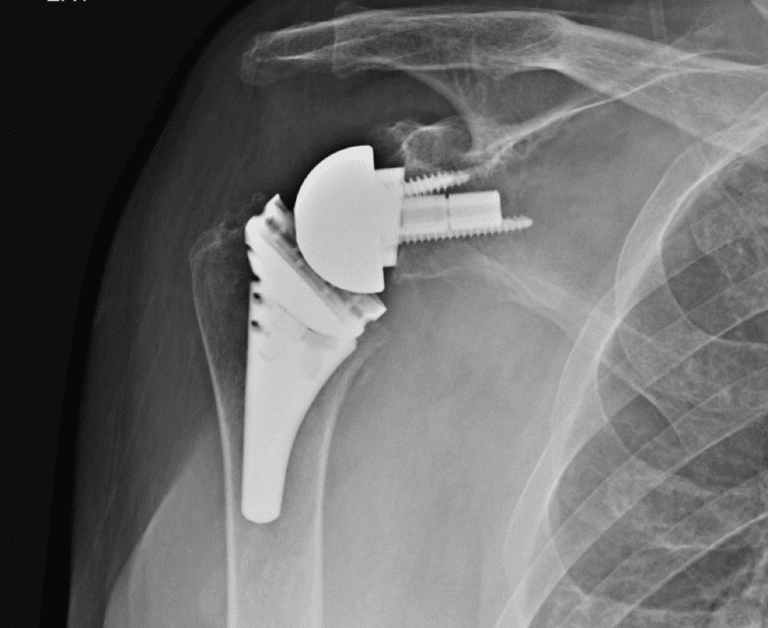

Arthrex, Apex

Selected